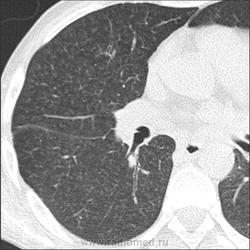

Прозрачность обеих легких равномерно неинтенсивно снижена за счет наличия множественных, плохо дифференцируемых мелкоочаговых теней, сливающихся между собой и расположенных главным образом во внутренних отделах легких, ближе к корням легких, образуя картину «бабочки». Сосудистый рисунок диффузно усилен, в виде радиальных извитых теней за счет перибронхиальной и периваскулярной инфильтрации. Линейные тени пластинчатых ателектазов. Корни легких малоструктурны. Органы средостения не смещены. Сердечная тень не увеличена."

Я не вижу "Бабочку", а Вы?

Из-за почечной недостаточности контрастирования не будет. Такая картина в легких мне впервые попадается. Есть несколько вариантов, но очень хочется услышать мнения коллег! Какие будут мысли?

Михаил Анатольевич, это всё замечательно, то есть наоборот для пациента. Вопрос: как гипо- и авитамоноз В1 проявляются в данном случае в легочном рисунке? Пряник не жалко: ЧТО С ЛЕГКИМИ???

В легких - рентгенограмму я описала как усиление за счет интерстициального компонента. Корень кажется обрубленным: из-за асцита высоко стоит диафрагма, нижние отделы легких поджаты. Пневмосклероза я не вижу. А по КТ не знаю, как интерпретировать: интерстициальный отек, токсический васкулит?

Михаил Анатольевич, Ваши комменты нельзя использовать в протоколе рентгенологического исследования . Что посоветуете писать РЕНТГЕНОЛОГУ при описании подобной рентгенограммы? Норму? Отек легких? Гиповитаминоз и гипоальбуминемию я не могу написать в протоколе, это ясно клиницисту и без меня...

Тогда, учитывая всё вышесказанное, вероятно интерстициальный отёк ( гипопротеинемия, почечная недостаточность, токсическое поражение...)

Парочка моих шаблонов, наверное первый соответствует настоящему состояниюПрозрачность обеих легких равномерно неинтенсивно снижена за счет наличия множественных, плохо дифференцируемых мелкоочаговых теней, сливающихся между собой и расположенных главным образом во внутренних отделах легких, ближе к корням легких, образуя картину «бабочки». Сосудистый рисунок диффузно усилен, в виде радиальных извитых теней за счет перибронхиальной и периваскулярной инфильтрации. Линейные тени пластинчатых ателектазов. Корни легких малоструктурны. Органы средостения не смещены. Сердечная тень не увеличена.

Прозрачность обеих легких неравномерно, преимущественно в нижних отделах, неинтенсивно снижена за счет наличия множественных, плохо дифференцируемых крупноочаговых теней, сливающихся между собой и расположенных главным образом во внутренних отделах легких, ближе к корням легких, образуя картину «бабочки». В прикорневых и паравертебральных отделах значительное усиление сосудистого рисунка, размытого грубопетлистого, обусловлено венозным полнокровием. Тени венозных сосудов определяются, как поперечно расположенные полосы с нерезкими контурами, преимущественно в нижних отделах. Определяются горизонтальные линии Керли вследствие интерстициального отека междольковых перегородок Корни легких расширены малоструктурны. Органы средостения не смещены. Сердечная тень увеличена в поперечнике, талия сглажена, аорта уплотнена, умеренно развернута

Я не вижу "Бабочку", а Вы?